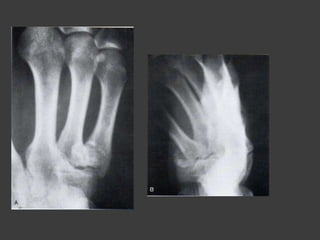

Fx en la base del metacarpiano

 Fx por avulsión de la base del segundo

y tercer metacarpianos

 Fx – luxaciones de la articulación CMC

del dedo meñique

 Luxaciones CMC multiples